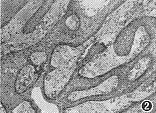

鳞状乳头型颅咽管瘤在镜下的典型表现为成熟的复层鳞状上皮细胞位于疏松的结缔组织基质中,上皮自基底膜向梁柱的中心或表面演变,细胞渐变扁平,形成许多多角形的粉红色的角化细胞,中央可见细胞核(图1)。在囊性鳞状乳头型中,构成囊壁的某些区域甚至只有2层上皮细胞相贴,类似成釉质细胞型的镜下表现,但其细胞核无“栅栏状”排列(图2,3)。在间质的纤维血鞘中,炎细胞浸润很常见。所有此型均不见有胆固醇裂隙,11例可见有基质角化,3例有矿物盐沉积,6例有微囊腔形成。

图2 鳞状乳头型颅咽管瘤,构成囊壁的上皮局部变薄,但基底膜上的细胞核无“栅栏状”排列